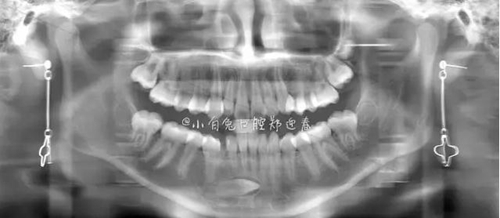

本案:患兒,女,14歲,因牙齒矯正來院,檢查見83滯留,43未見萌出,拍片發(fā)現(xiàn):43埋伏阻生于31、41、42根尖下方,按照正畸診療計劃,擬行43拔除術(shù)。

全景片